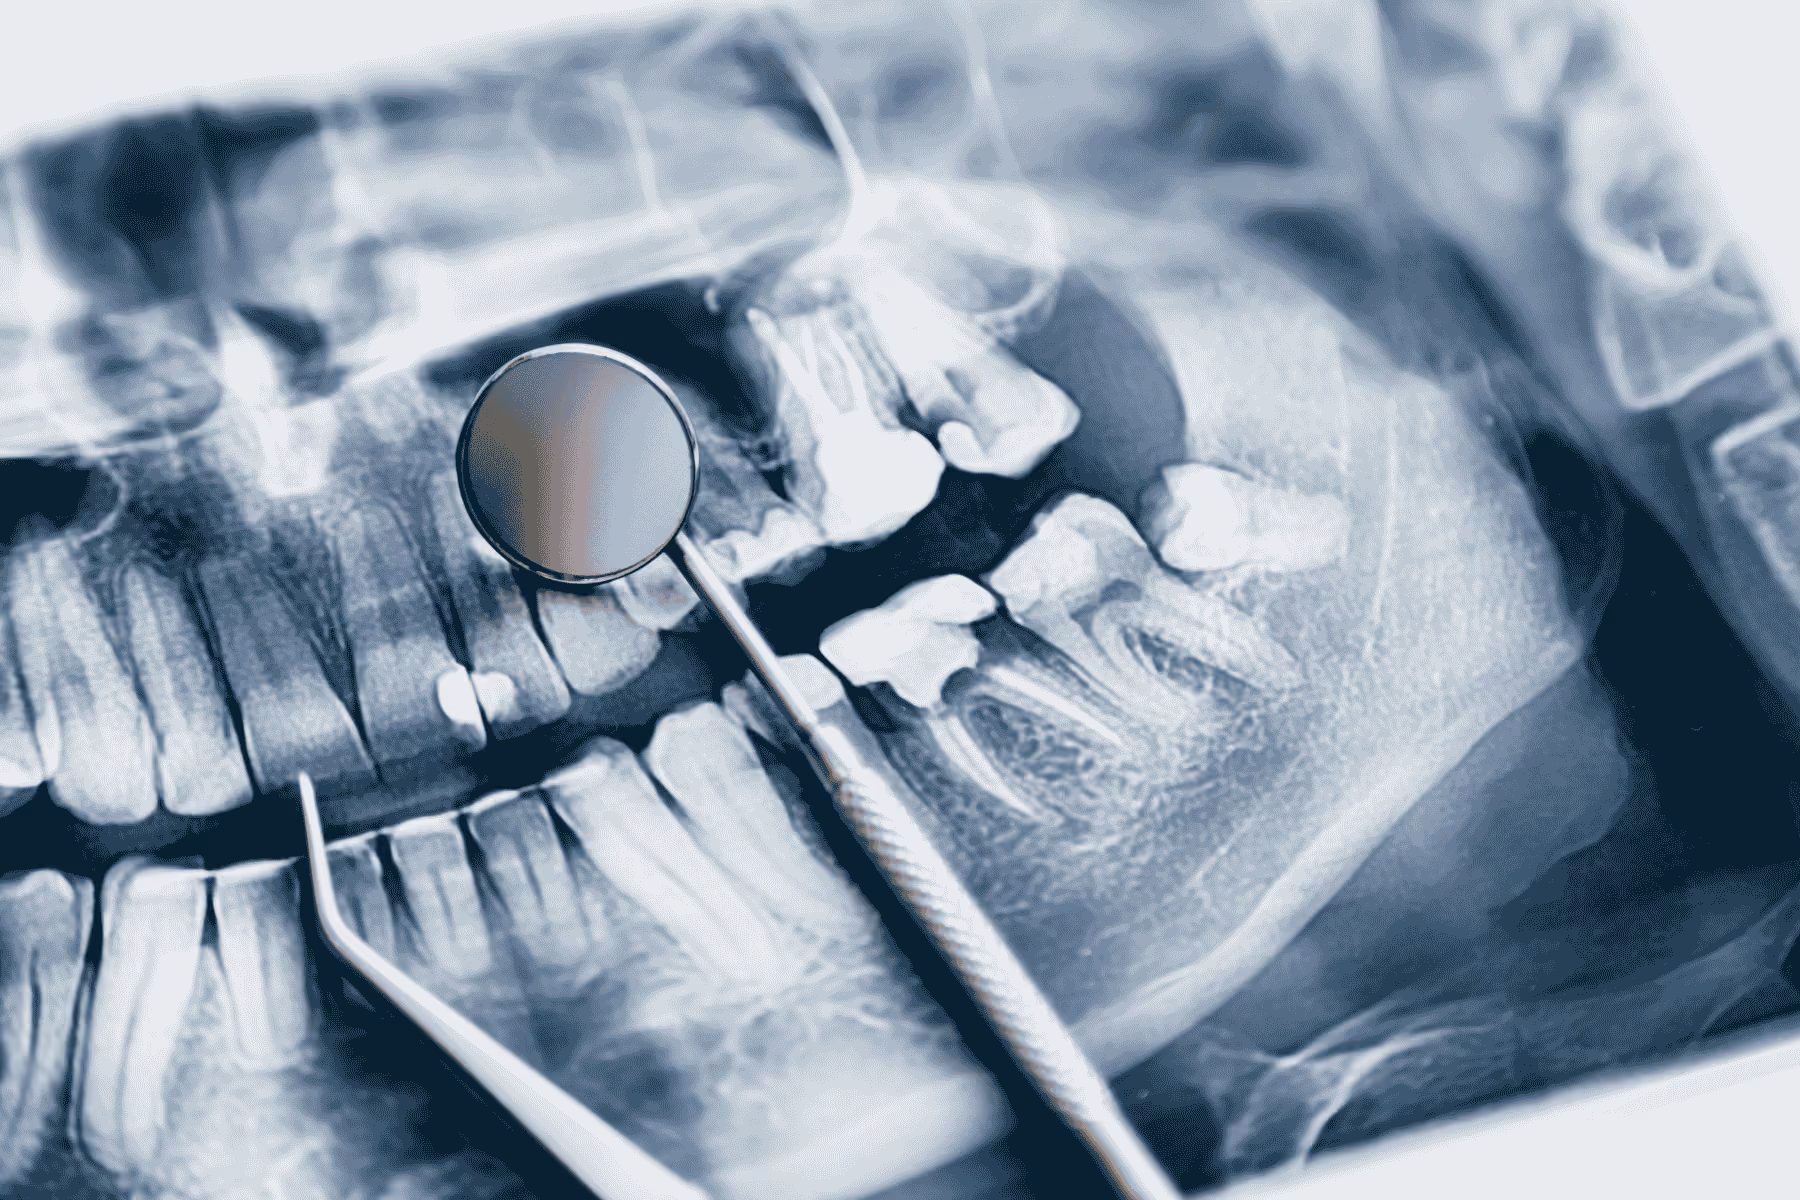

A CBCT scan (Cone Beam Computed Tomography) produces highly detailed 3D images of your oral anatomy, including your teeth, jawbone, soft tissues, sinuses, and nerves. This makes it an essential part of treatment, as it can detect any abnormalities or occurrences of bone resorption.

As the implant is inserted directly into the jaw, the dentist must take pictures of the area ahead of the procedure to pre-plan placement and assess for any complications like insufficient bone density. Read how to know if you need a bone graft.Without understanding the density of bone beforehand, a dentist cannot confidently guarantee that your implant will successfully integrate with the bone.As bone loss is common in patients who have worn dentures for a while or ignored gaps in their mouth, it’s an area of your treatment plan that requires the most preparation and thought.